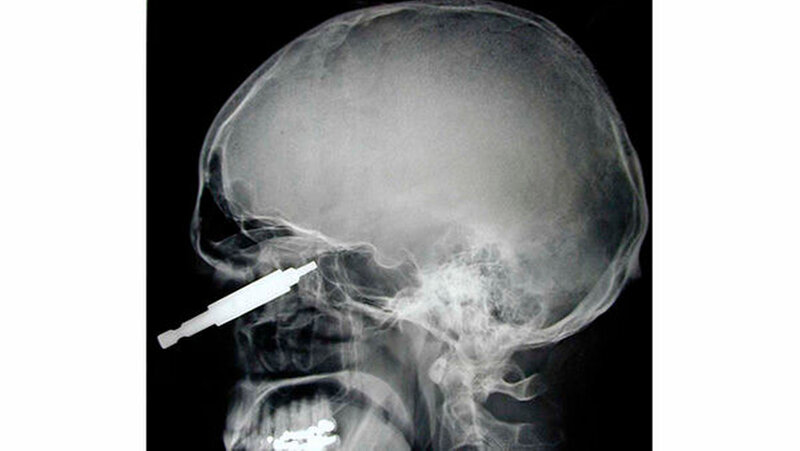

Vom Bohrer im Kopf bis zum Schlüssel in der Kieferhöhle: Die MKG-Chirurgen der Charité haben ausgewählte Patientenfälle mit Fremdkörpern im Gesicht zusammengestellt. In unserer Fotostrecke finden Sie die eindrucksvollen Aufnahmen.